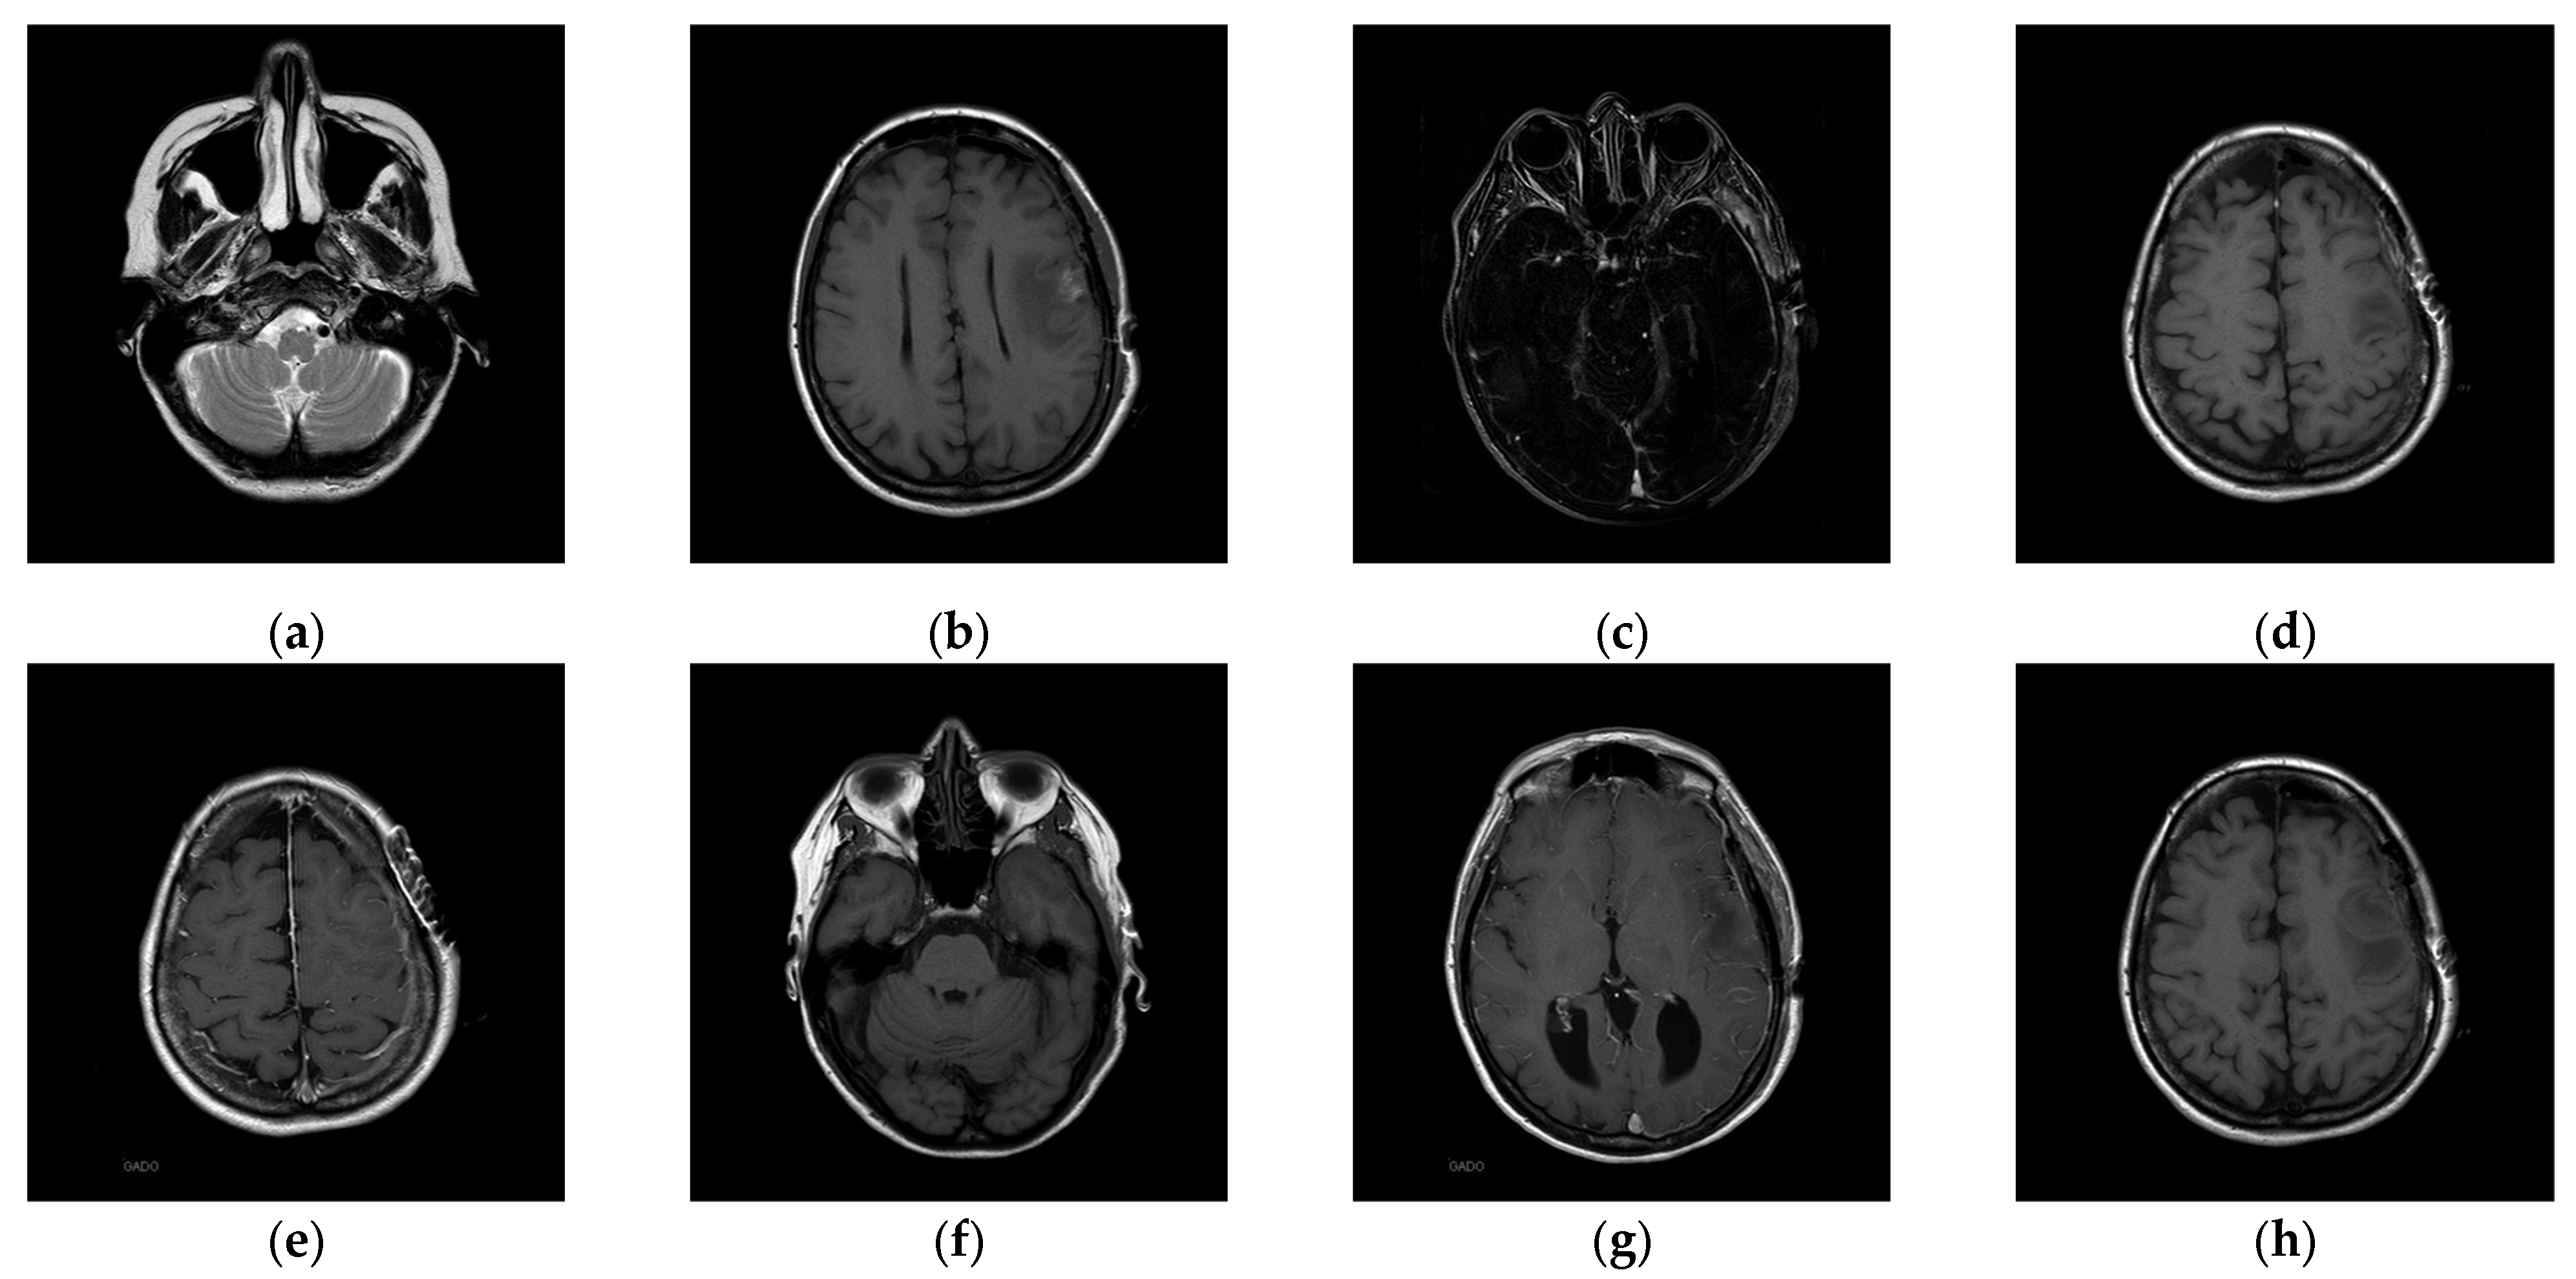

The experiments were conducted on two systems. The first system ran on Ubuntu 22.04, equipped with an Intel i7-9700KF CPU @ 3.60GHz (8 cores), an Nvidia GeForce RTX 3090 GPU, 32 GB of RAM, and Pytorch (https://pytorch.org/) for the experimentation. The second system, called the Type 1 device, is a notebook with an Intel(R) Core (TM) i7-10510U CPU @1.80 GHz 2.30 GHz, 16.0 GB RAM, 64-bit Windows operation system, and GPU MX 250. The third system, called the Type 2 device, is a notebook with an 11th Gen Intel(R) Core(TM) i5-11400H @ 2.70 GHz 2.69 GHz, 24.0 GB RAM, 64-bit Windows operation system, and GPU Nvidia GeForce 3060. The second system is a notebook that was released around 2019 or early 2020. The third system is also a notebook that was released in early 2021. The two systems were used to simulate resource-constrained environments. Different medical and test images were used as the test images to evaluate the performance of our proposed scheme and to make comparisons between our scheme and Qin et al.’s scheme [20]. In the first experiment, eight medical images, which are MRI scans of the brain, were randomly selected from the Osirix database [21] as test images and are presented in Figure 10 to demonstrate the performance of our proposed scheme in detail. In the second experiment, one hundred medical images, which are also MRI scans of the brain, were randomly selected from the Osirix database [21] to form Dataset 1 and Dataset 2, as shown in Figure 11, to prove the stable performance of our proposed scheme. In the third experiment, six general grayscale images, sized 512 × 512, demonstrated in Figure 12, were used to compare with those offered by Qin et al.’s scheme [20]. The logo depicted in Figure 13a was used as the watermark for the first and the second experiments and Figure 13b was used as the watermark for the third experiment.

Figure 10. Eight medical test images. (a) 10.png; (b) 11.png; (c) 14.png; (d) 16.png; (e) 19.png; (f) 26.png; (g) 31.png; (h) 57.png.